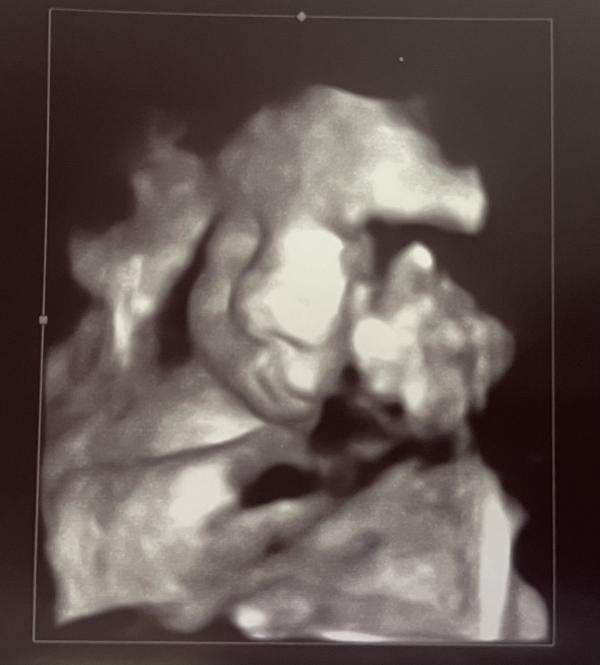

Привет, 40 недель! Сегодня ПДР, что дальше? Ждем малыша, скоро роды!

Ну привет, 40 недель 🙈

Сегодня ПДР 😳